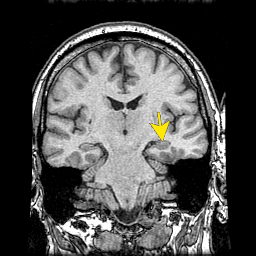

Memorisation. image: The Whole Brain Atlas